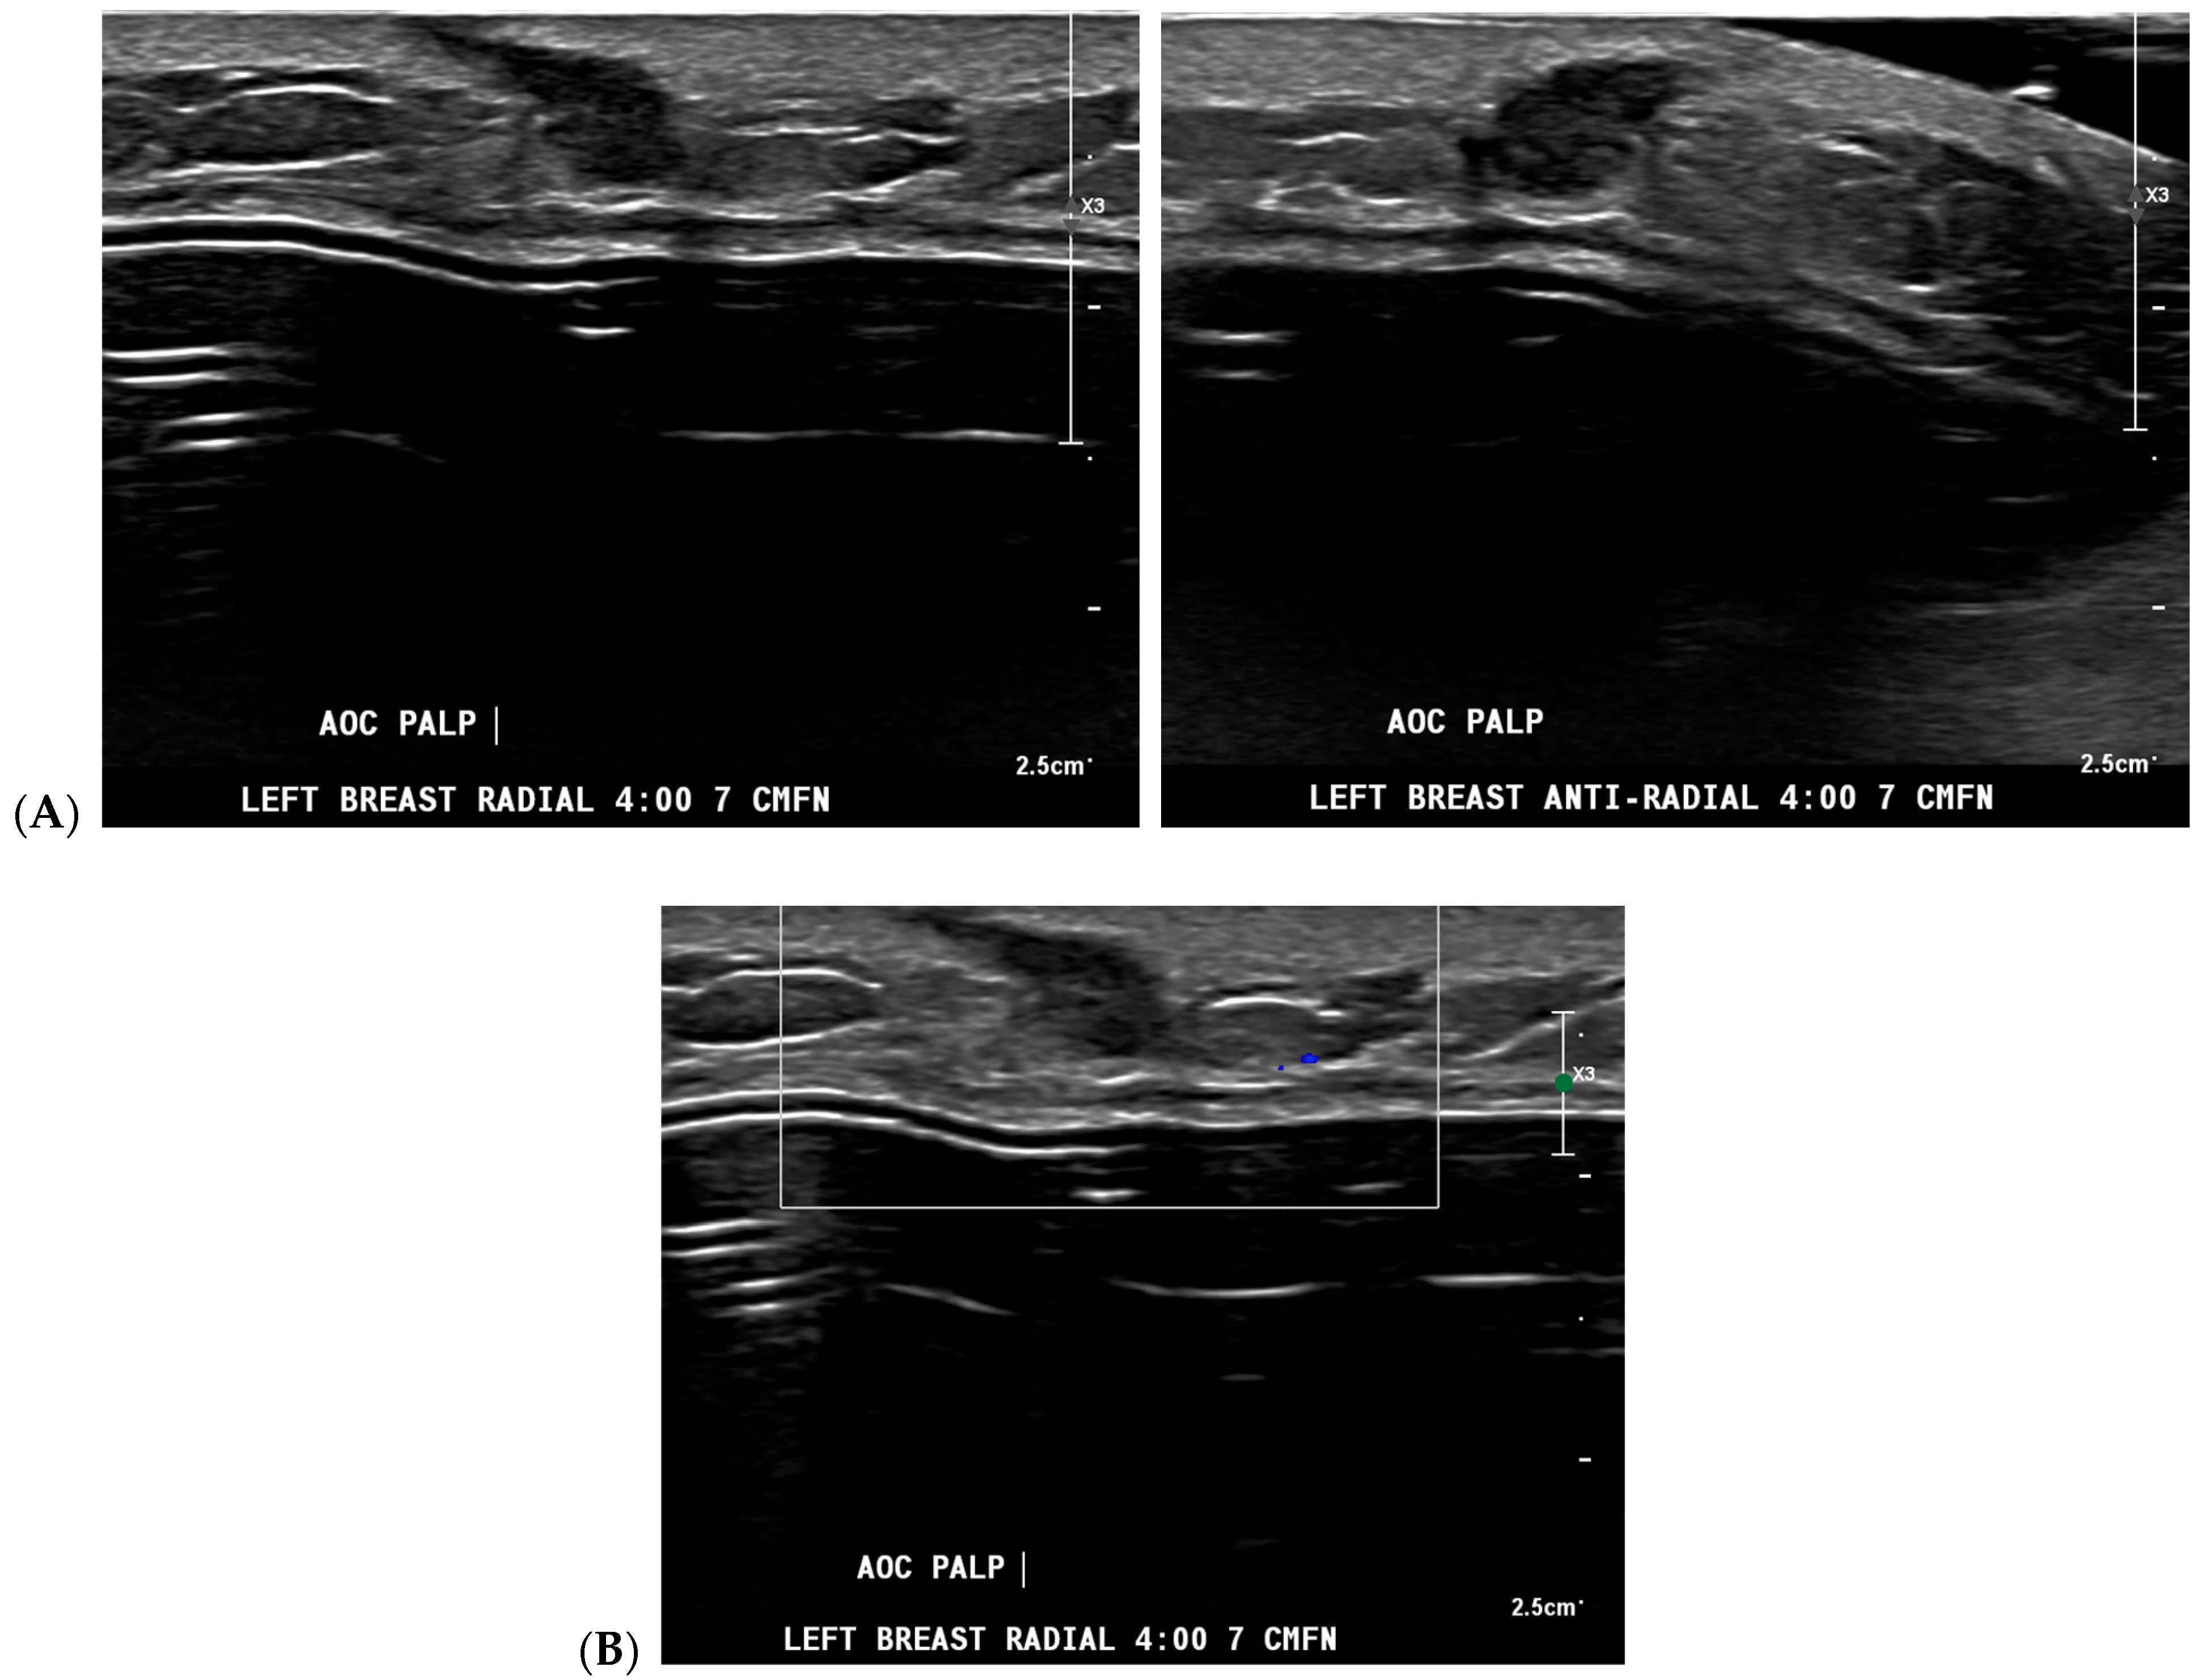

Figure 3.

A new cancer diagnosis appropriately classified as “malignant” by artificial intelligence (AI): This patient in her 40s with a history of left breast carcinoma diagnosed 1 year prior, status post-left mastectomy with chemotherapy and hormonal therapy, presented with a palpable abnormality in the superficial lower outer left breast. No new or suspicious findings were seen on the patient’s diagnostic mammogram. Correlating with the patient’s concern about a palpable lump, diagnostic ultrasound revealed an irregularly shaped, hypoechoic mass with angular margins that are non-parallel (A), and Doppler shows no vascularity (B). The AI program Koios recognized this mass as “Probably Malignant” (C). This was returned as biopsy-proven invasive ductal carcinoma. Images obtained from the Icahn School of Medicine at Mount Sinai.